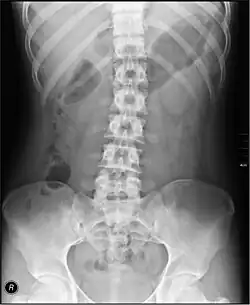

Radiographie de l'abdomen sans préparation

La radiographie de l'abdomen sans préparation, plus souvent abrégé « Abdomen sans préparation » (ASP) ou abdomen à blanc consiste à radiographier l'abdomen sans produit de contraste, contrairement au transit baryté ou au lavement baryté.